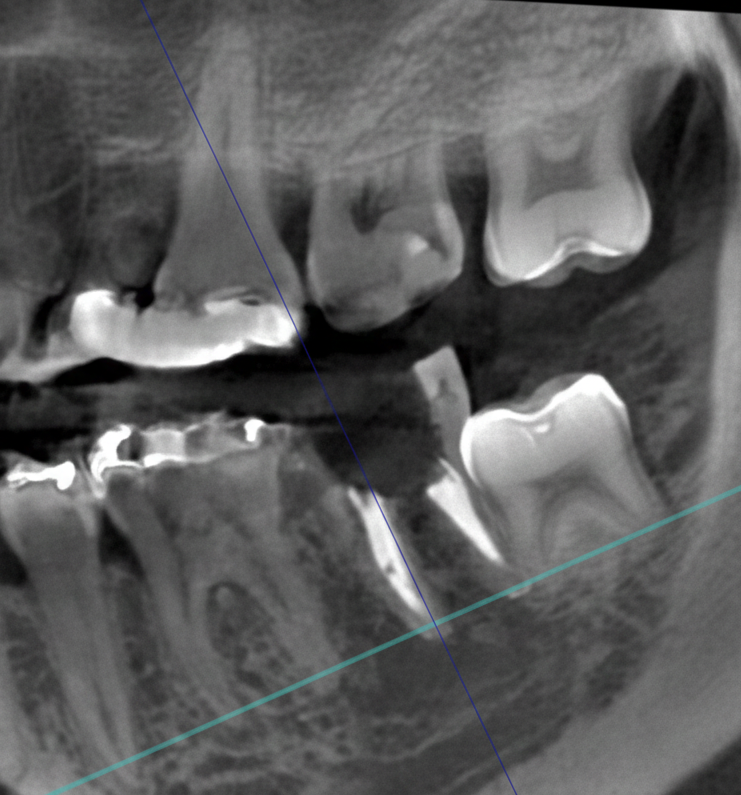

歯の神経や根っこに潜む細菌をきれいに取り除く、根管治療。CT画像では、根の本数や神経の入っている管の方向、そして位置を正確に把握することができます。また、細かい根の破折も発見できるので、早期治療が可能になります。

歯科用CTを親知らずの抜歯に利用することで、神経までの正確な距離や、周囲の炎症の程度、病巣の有無や大きさ、位置なども判断・考慮して、治療を行うことができます。また埋伏歯などの位置なども精密に判断できるので、余分な切開や骨の切削などを避けることができます。